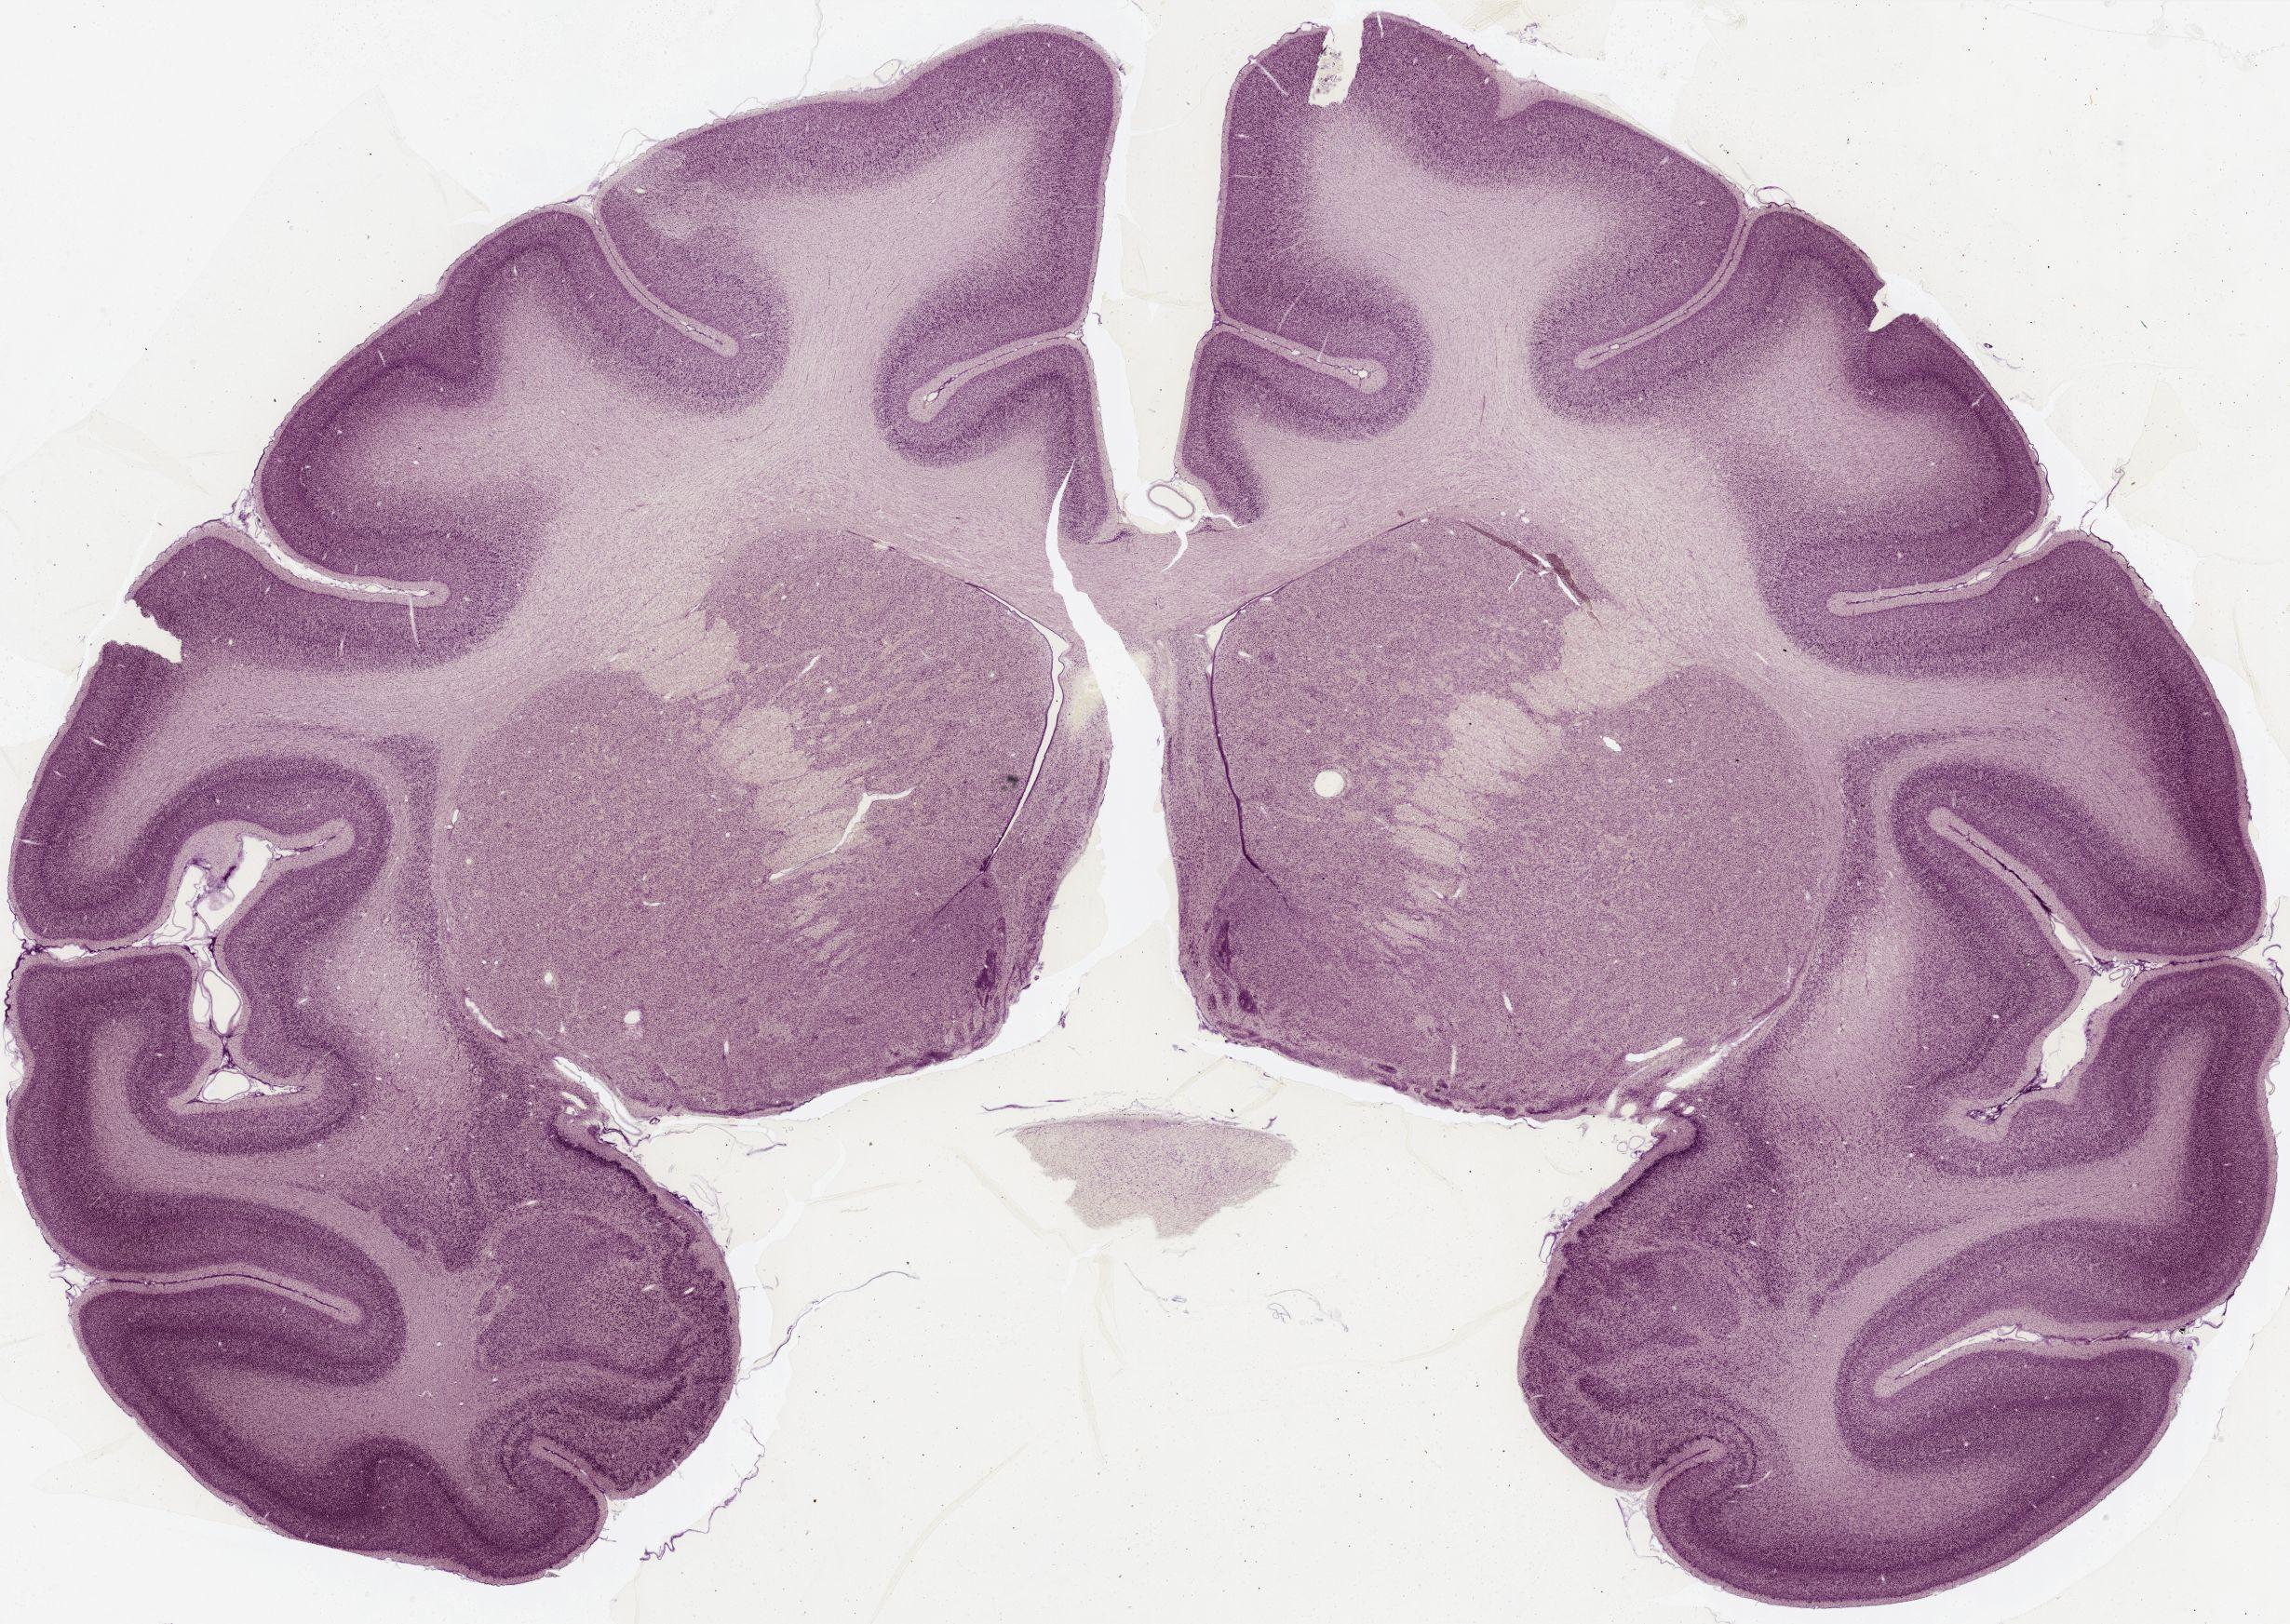

Datasets -> Macaca Mulatta -> Nissl, coronal, histo, Whole-Brain, adult [ Metadata ] · Source: Edward G. JonesDisplaying Sections 1 thru 40 of 56 Sections for this DatasetPages: 1 2 1339 - labeled 1301 - labeled 1251 - labeled 1201 - labeled 1151 - labeled 1102 - labeled 1051 - labeled 1040 - labeled 1020 - labeled 1006 - labeled 1001 - labeled 0982 - labeled 0975 - labeled 0958 - labeled 0951 - labeled 0941 - labeled 0924 - labeled 0920 - labeled 0901 - labeled 0894 - labeled 0878 - labeled 0875 - labeled 0859 - labeled 0851 - labeled 0845 - labeled 0824 - labeled 0823 - labeled 0801 - labeled 0800 - labeled 0785 - labeled 0781 - labeled 0771 - labeled 0770 - labeled 0732 - labeled 0721 - labeled 0720 - labeled 0701 - labeled 0682 - labeled 0680 - labeled 0666 - labeledPages: 1 2